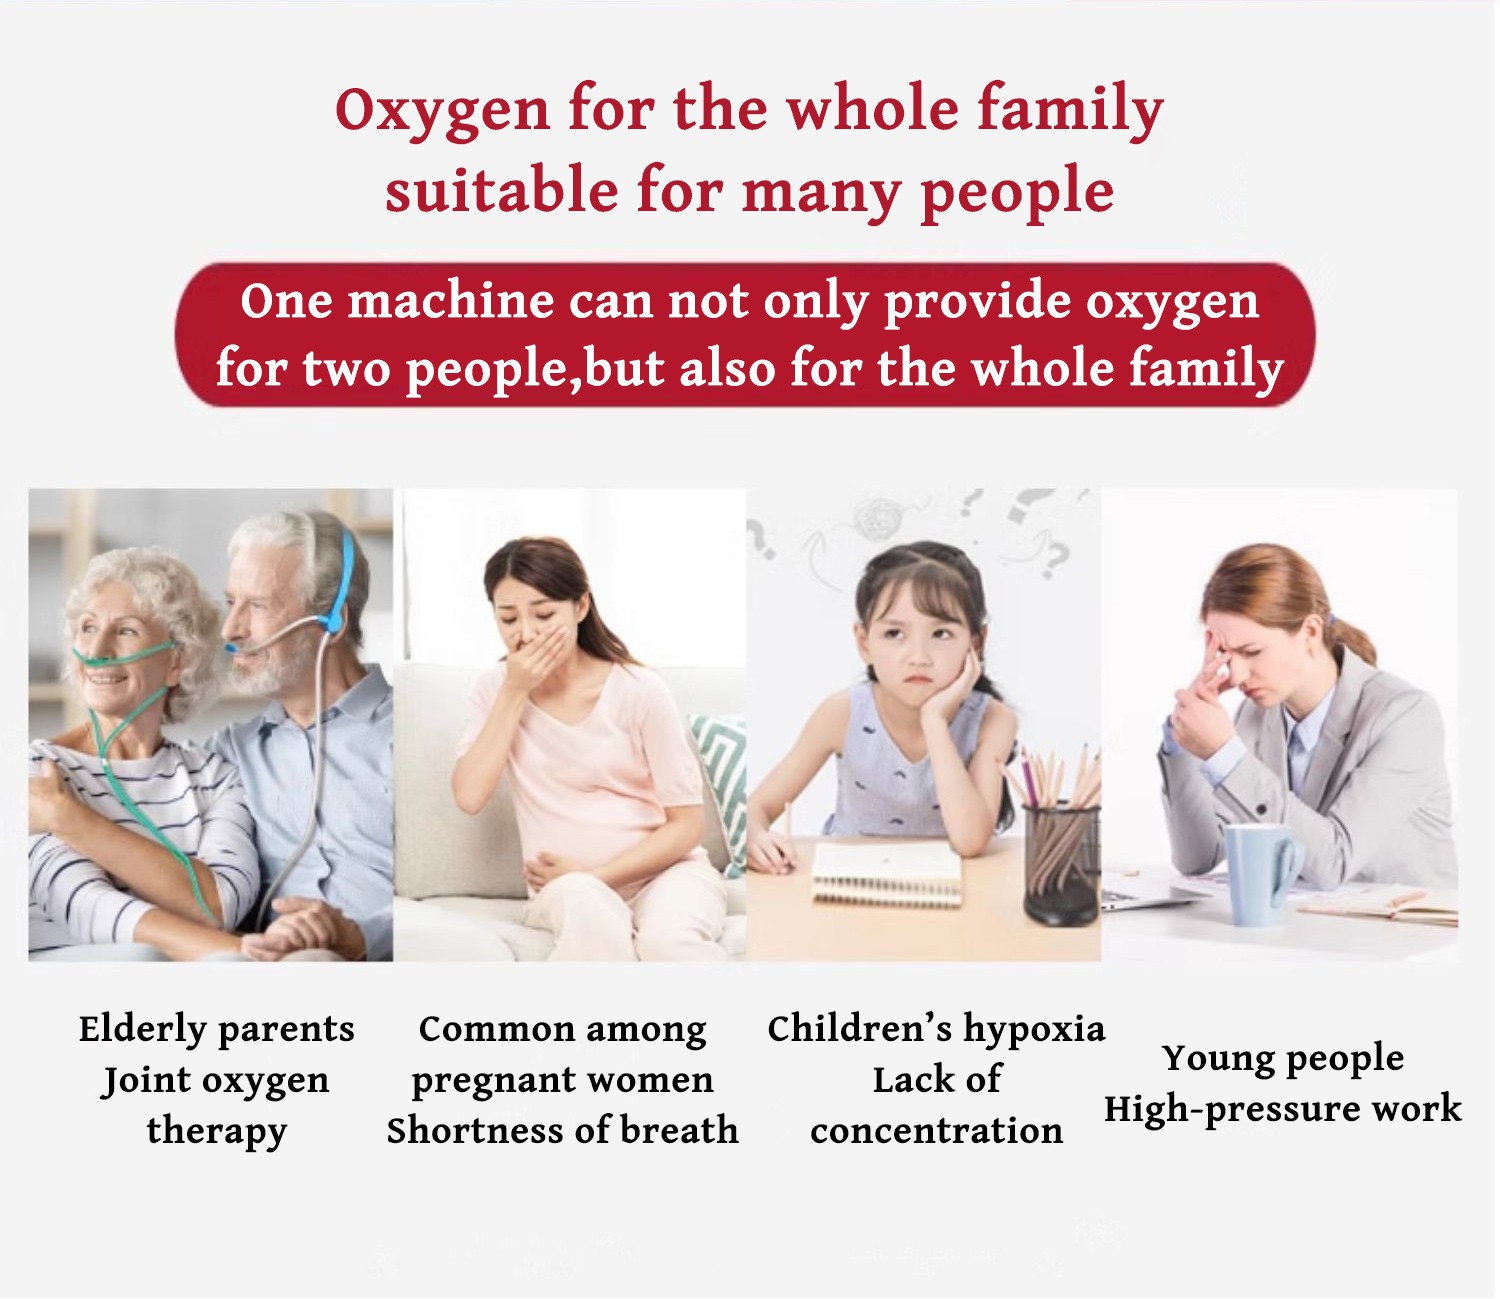

Επί του παρόντος, ο αριθμός των ανθρώπων που πάσχουν από αναπνευστικές ασθένειες στον κόσμο είναι πολύ υψηλός, καθώς οι αναπνευστικές ασθένειες περιλαμβάνουν διάφορες ασθένειες όπως το άσθμα, η χρόνια αποφρακτική πνευμονοπάθεια (ΧΑΠ), ο καρκίνος του πνεύμονα, η πνευμονία κ.λπ. Οι παγκόσμιες στατιστικές δείχνουν ότι οι αναπνευστικές ασθένειες σκοτώνουν εκατομμύρια ανθρώπους κάθε χρόνο, συμπεριλαμβανομένων ασθενών όλων των ηλικιών, σύμφωνα με εκτιμήσεις του Παγκόσμιου Οργανισμού Υγείας (ΠΟΥ). Τα στοιχεία ποικίλλουν ανά χώρα και περιοχή, αλλά γενικά, οι αναπνευστικές ασθένειες αποτελούν σημαντική πρόκληση για την υγεία παγκοσμίως.

Ο συμπυκνωτής οξυγόνου που πουλάμε είναι ένα προϊόν που αναπτύξαμε μετά από 5 χρόνια έρευνας και ανάπτυξης. Μετά την κυκλοφορία του, έλαβε ομόφωνους επαίνους από αμέτρητους αναπνευστικούς ασθενείς και πουλήθηκε σε εκατοντάδες χώρες σε όλο τον κόσμο.